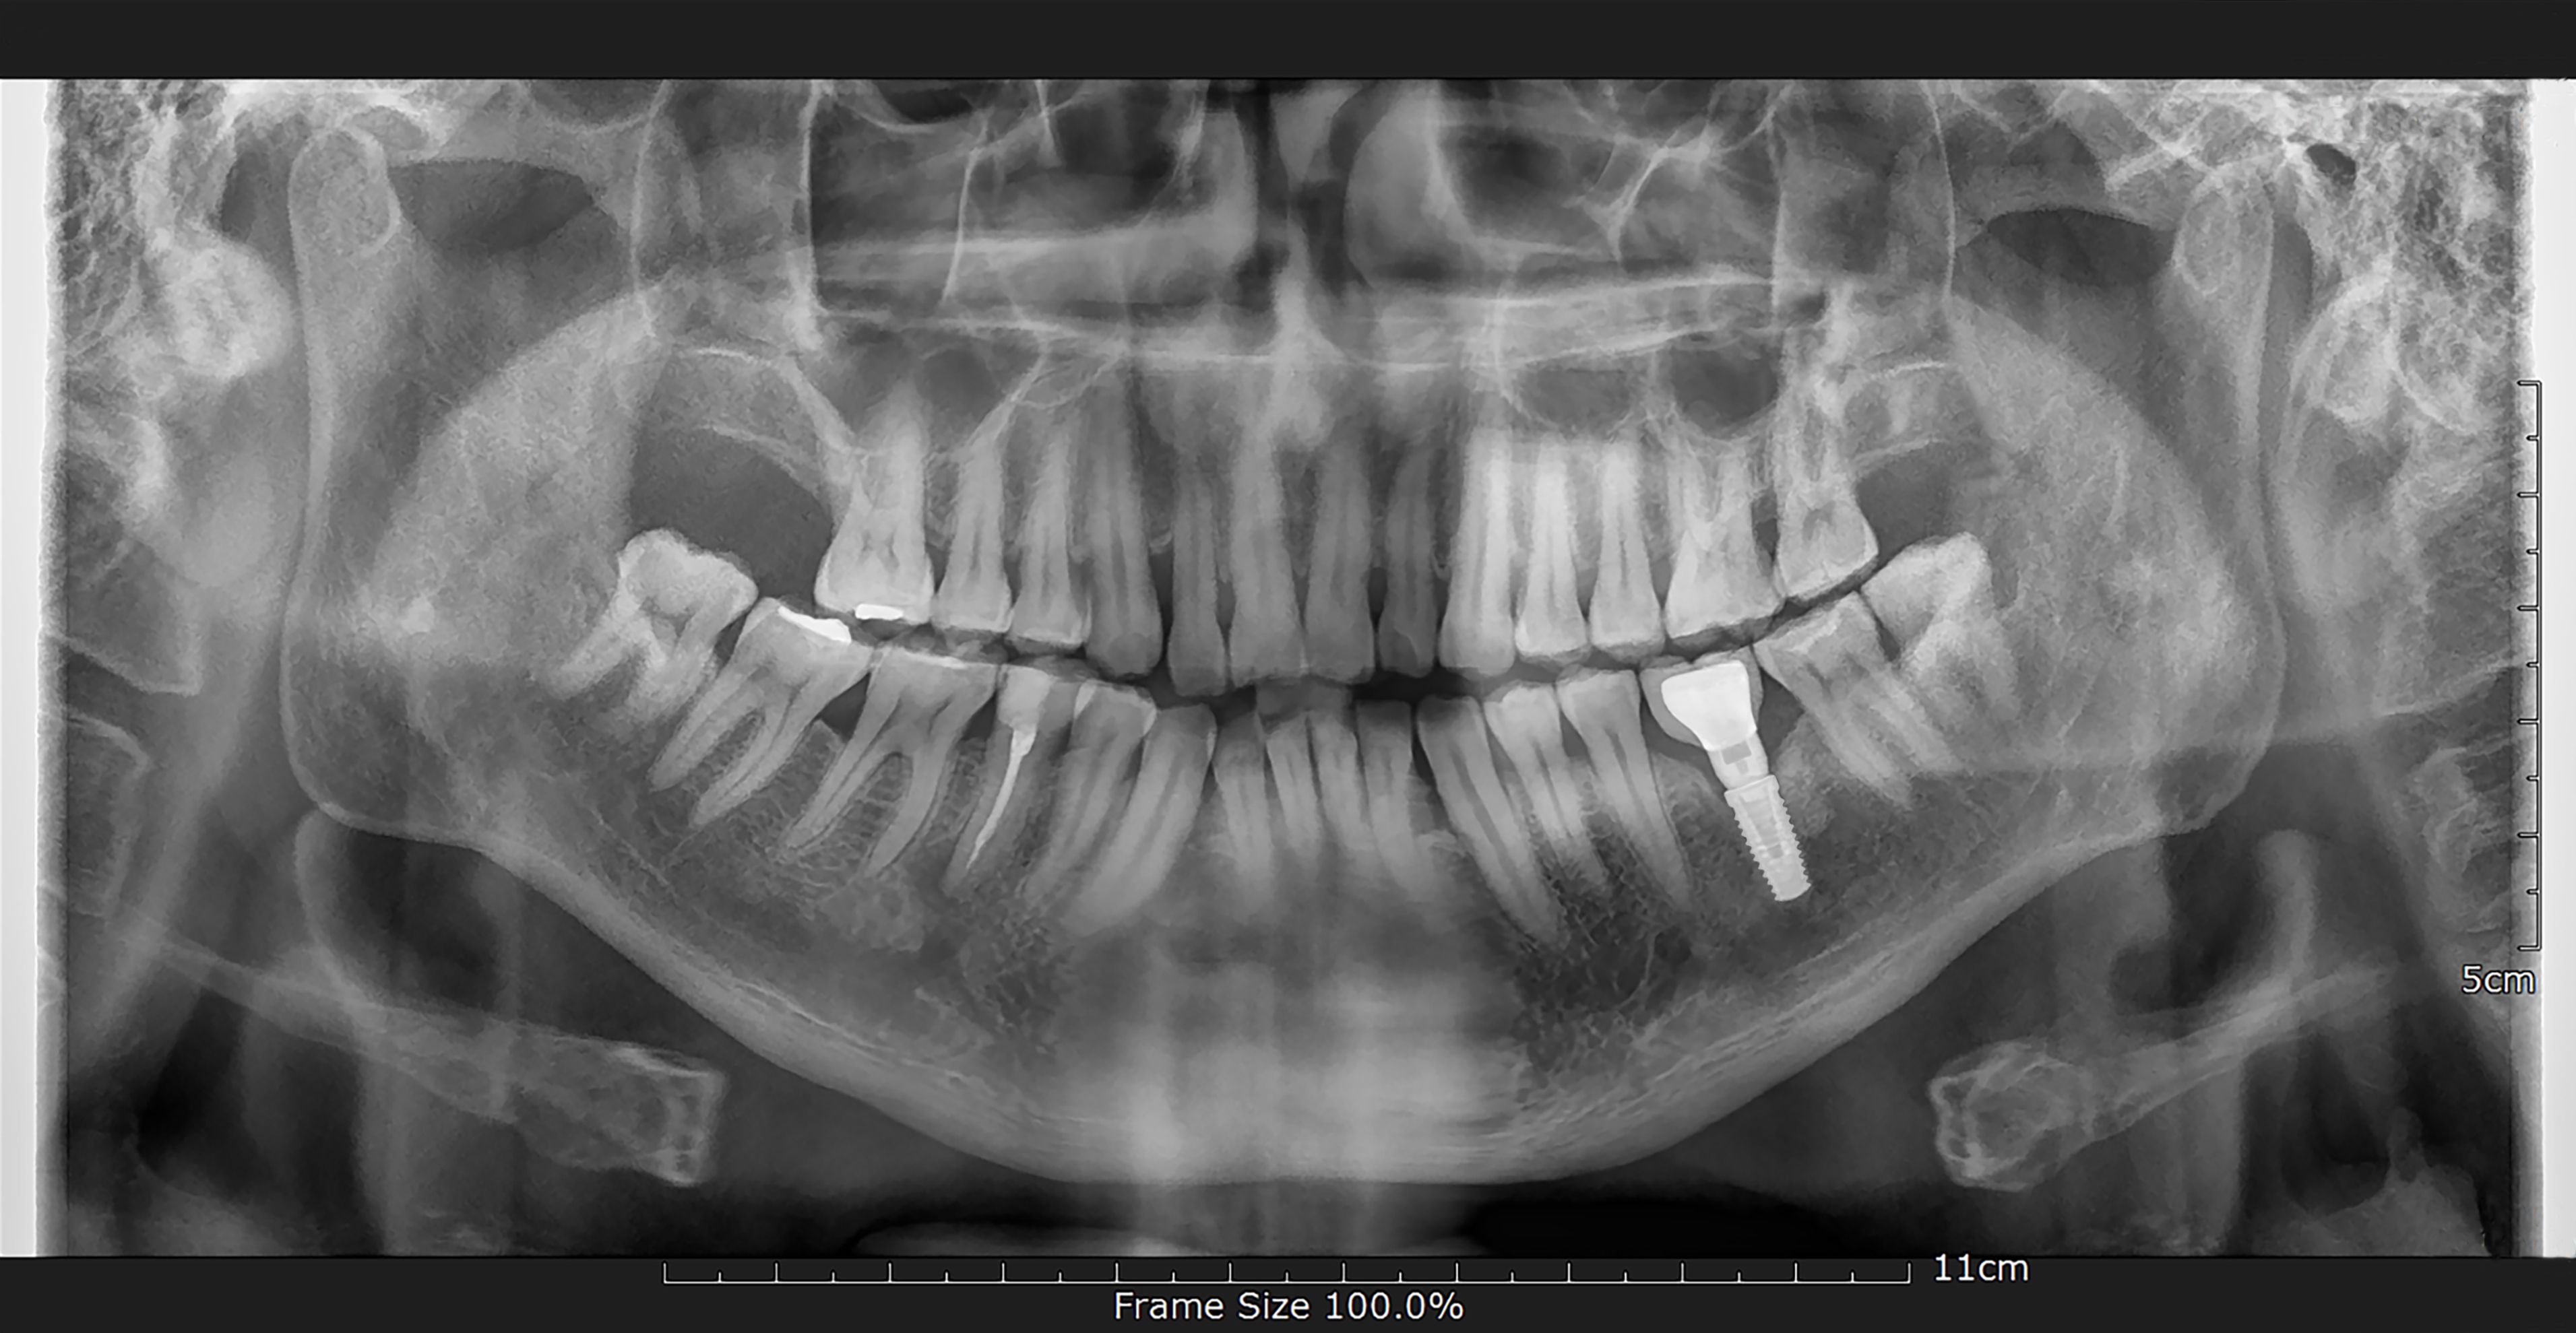

- Initial Consultation: A comprehensive examination, including X-rays, to determine suitability.

- Surgical Placement: The titanium post is embedded into the jawbone under local anesthesia.

- Osseointegration: A healing period where the implant fuses with the bone, usually lasting a few months.

- Sufficient Bone Density: Adequate jawbone is necessary to support the implant.